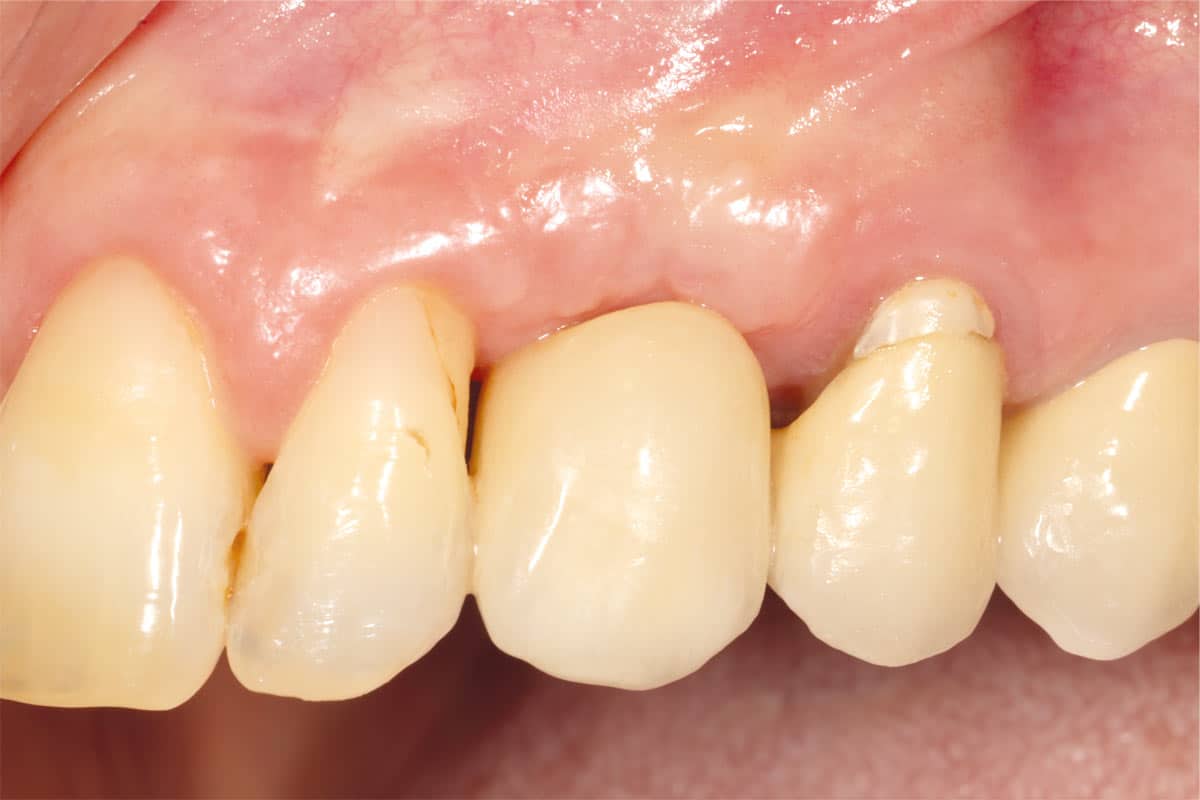

At the 6-month follow-up, clinical and radiographic evaluations demonstrated pronounced new bone formation and favourable soft tissue integration, indicating successful regenerative outcomes. By the 12-month follow-up, bone regeneration had advanced even further, and implant stability was significantly strengthened, confirming the procedure’s lasting success. A CBCT scan at 6 months revealed promising results, which were even more striking at the 12-month mark, demonstrating optimal bone integration and implant stability.